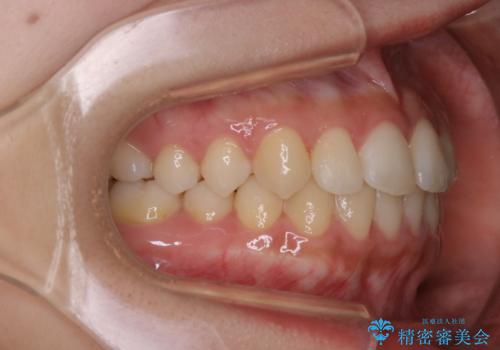

- 矯正治療が終了したため、クリーニングでもきれいにしたいとのことでした。PMTC60分コースを行いました。

矯正治療が終わり、せっかくきれいになった歯並びも、虫歯・歯周病などになってしまっては元も子もありません。

矯正治療やセラミックなどによる被せ物の治療終了のタイミングではクリーニングを行い、汚れや着色の除去、歯と歯の間・歯と歯肉との境目などのケアをしっかりすることをおすすめしています。